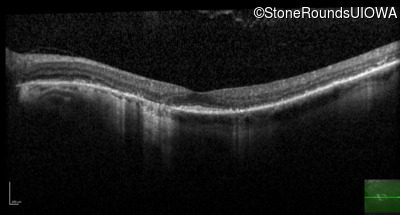

Optical Coherence Tomography - Right - 20/63

Exemplar / OCT Stack